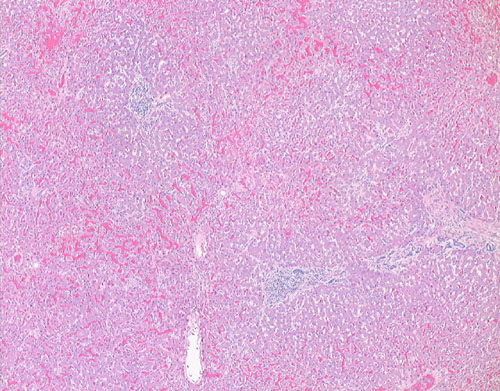

52. Acute Myocardial Infarct